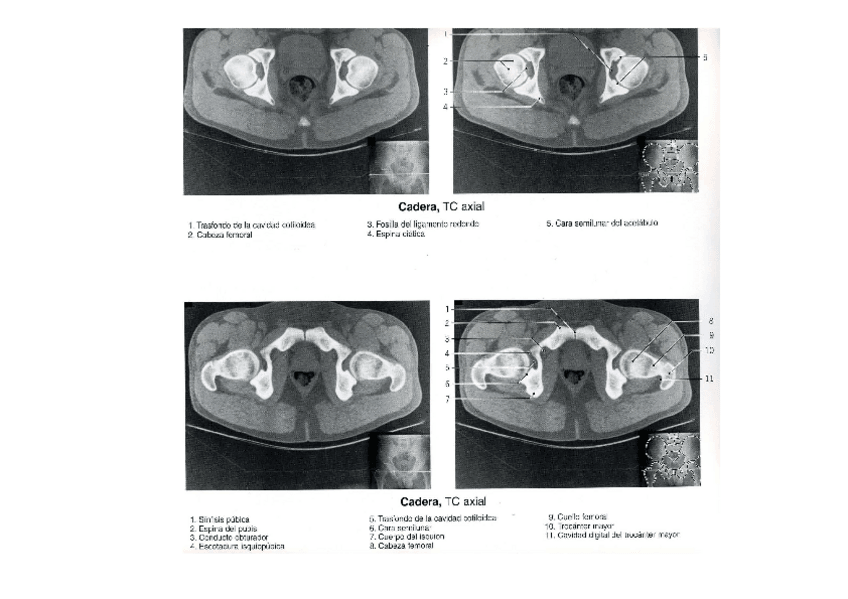

apuntes

musculos TC

He publicado nuevos apuntes de Técnicas de Tomografía Computarizada y Ecografía: musculos TC

MALUCS-TC-Modo-de-compatibilidad.pdf

MUSCULS-maluc-Modo-de-compatibilidad.pdf